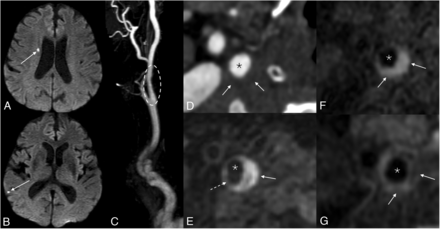

Because it is now known that many symptomatic plaques are nonstenotic by the NASCET criteria (Fig 4), there is a growing call for the modification of treatment guidelines. Specifically, many believe that imaging markers of plaque vulnerability should be considered in the determination of treatment eligibility. The most promising imaging features are IPH, ulceration, and maximum plaque thickness; LRNC, integrity of the fibrous cap, and some categories of intraplaque calcifications also have potential usefulness.55

Example of a symptomatic nonstenotic plaque. Axial DWI (A and B) of the brain demonstrates multiple tiny acute infarcts in the right cerebral hemisphere (arrows). 3D reformatted gadolinium bolus image (C) demonstrates a nonstenotic plaque in the proximal right ICA (dashed oval). Axial CTA image (D) shows a soft, noncalcified plaque. On MRA, MPRAGE image (E) shows that most of this plaque is composed of hemorrhagic material (solid arrow), with a small hypointense component representing a nonhemorrhagic lipid necrotic core (dashed arrow). Pre- (F) and postcontrast (G) T1 Cube images demonstrate a LRNC (solid arrows). Asterisks denote the vessel lumen.